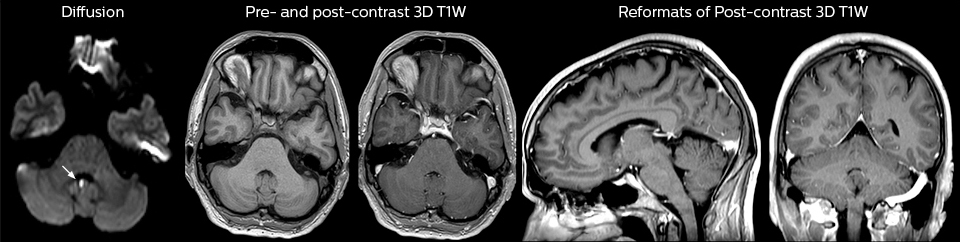

Dieser Patient wurde mit Kopfschmerzen vorstellig, die sich bei einer Flexion des Nackens verschlimmerten, und wir sehen hier eine Chiari-Malformation vom Typ I mit niedrig liegenden Kleinhirntonsillen sowie degenerativen zervikalen, thrombolytischen Veränderungen.

Eine Reihe von Protokollen wurde ausgearbeitet, um sicherzustellen, dass überweisende Ärzte die am besten geeignete MRT-Untersuchung anfordern. Die optimierten MRT-Protokolle umfassen auch die kontrastmittelverstärkte 3D-Bildgebung, die es den Neurochirurgen ermöglicht, während eines stereotaktischen Eingriffs im OP komfortabel auf die isotropen Daten zuzugreifen.